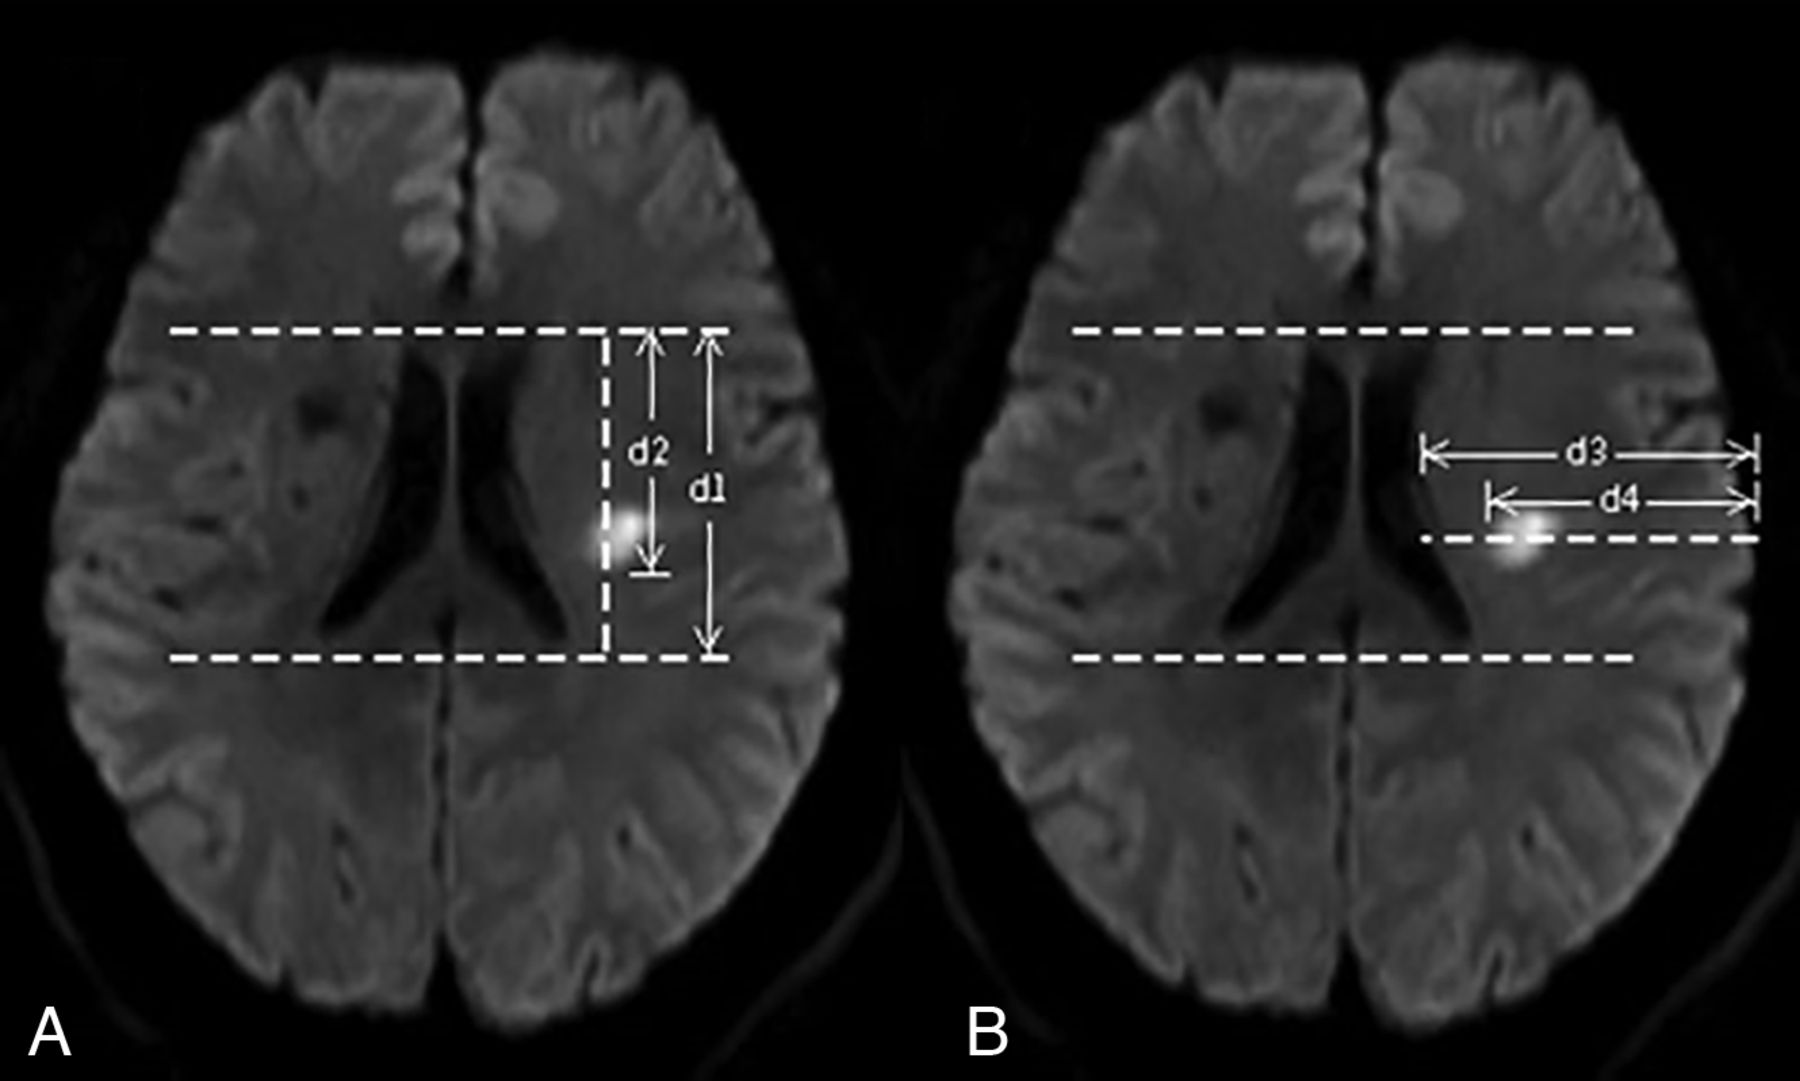

This study was performed by using a previously reported standard axial image template with 6 standard layers in the LSA territory. In this template, the first layer represents the lowest part of the basal ganglia region closest to the opening of the perforating branch of the middle cerebral artery, and the sixth layer represents the farthest level of the perforating artery. The anteroposterior and mediolateral localization of the lesion were assessed at the level of the second section from the top of the CR section showing the lateral ventricle on DWI. Two parallel tangents were drawn along both sides of the anterior and posterior horns of the lateral ventricles. As shown in Fig 2, we measured the longitudinal distance between the tangents (d1), the distance from the inferior edge of the lesion to the tangent of the superior horn of the lateral ventricle (d2), the horizontal distance from the lateral ventricle to the ipsilateral cerebral parenchyma passing through the innermost margin of the lesion (d3), and the horizontal distance from the innermost margin of the lesion to the edge of the ipsilateral cerebral parenchyma (d4). The posteriority index was defined as the d2/d1 ratio, and it indicated the anteroposterior localization of the lesions. The laterality index was defined as the d4/d3 ratio, and it indicated the mediolateral localization of the lesions (Fig 2). The lowest section and number of slices were also evaluated. On the basis of the lowest section and number of slices, SSSIs were categorized as pSSSI (lowest section ≤ 2), distal SSSI (lowest section > 2), small SSSI (number of slices < 3), and lSSSI (number of slices ≥ 3). Any degree of abnormality seen on an imaging assessment of the M1 segment of the MCA ipsilateral to the lesion was classified as parent artery disease (PAD),19,20 and cases that did not show such abnormalities were categorized as non-PAD. The Fazekas score was used to evaluate paraventricular and deep white matter hyperintensities. Severe white matter hyperintensity was defined if either score was ≥2.21 All images were reviewed independently by 2 physicians who were blinded to the clinical data. In cases where discrepancies arose, a final decision was reached by remeasuring.

The longitudinal distance between the tangents (d1) and the distance from the inferior edge of the lesion to the tangent of the superior horn of the lateral ventricle (d2) (A). The horizontal distance from the lateral ventricle to the ipsilateral cerebral parenchyma passing through the innermost margin of the lesion (d3) and the horizontal distance from the innermost margin of the lesion to the edge of the ipsilateral cerebral parenchyma (d4) (B).